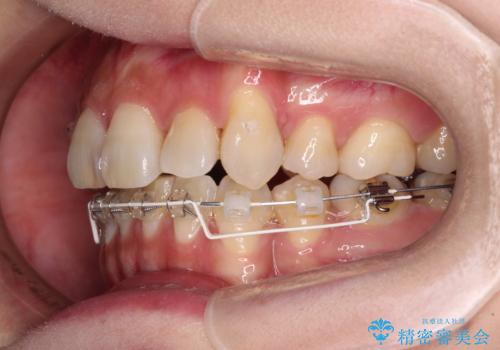

- ハーフリンガル

目立たない装置を希望されたので、上顎が裏側装置のハーフリンガルを選択し、上下左右の小臼歯(計4歯)を抜歯して矯正治療を行うこととしました。

補助装置を併用することで、八重歯を速やかに改善し、治療期間の短縮を図ることとしました。

ハーフリンガルでの矯正治療は、表側矯正よりも期間がかかることが多く、抜歯矯正では3年以上かかることも珍しくありません。

デコボコが強い一方で出っ歯ではなかったため、抜歯したスペースを容易に閉じることができ、短期間での治療となりました。